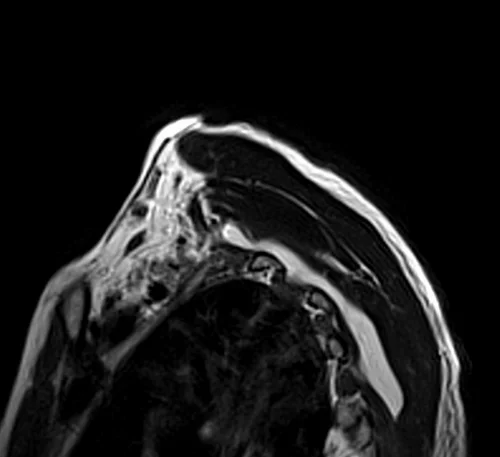

MRI brachial plexus sagittal oblique T2 images